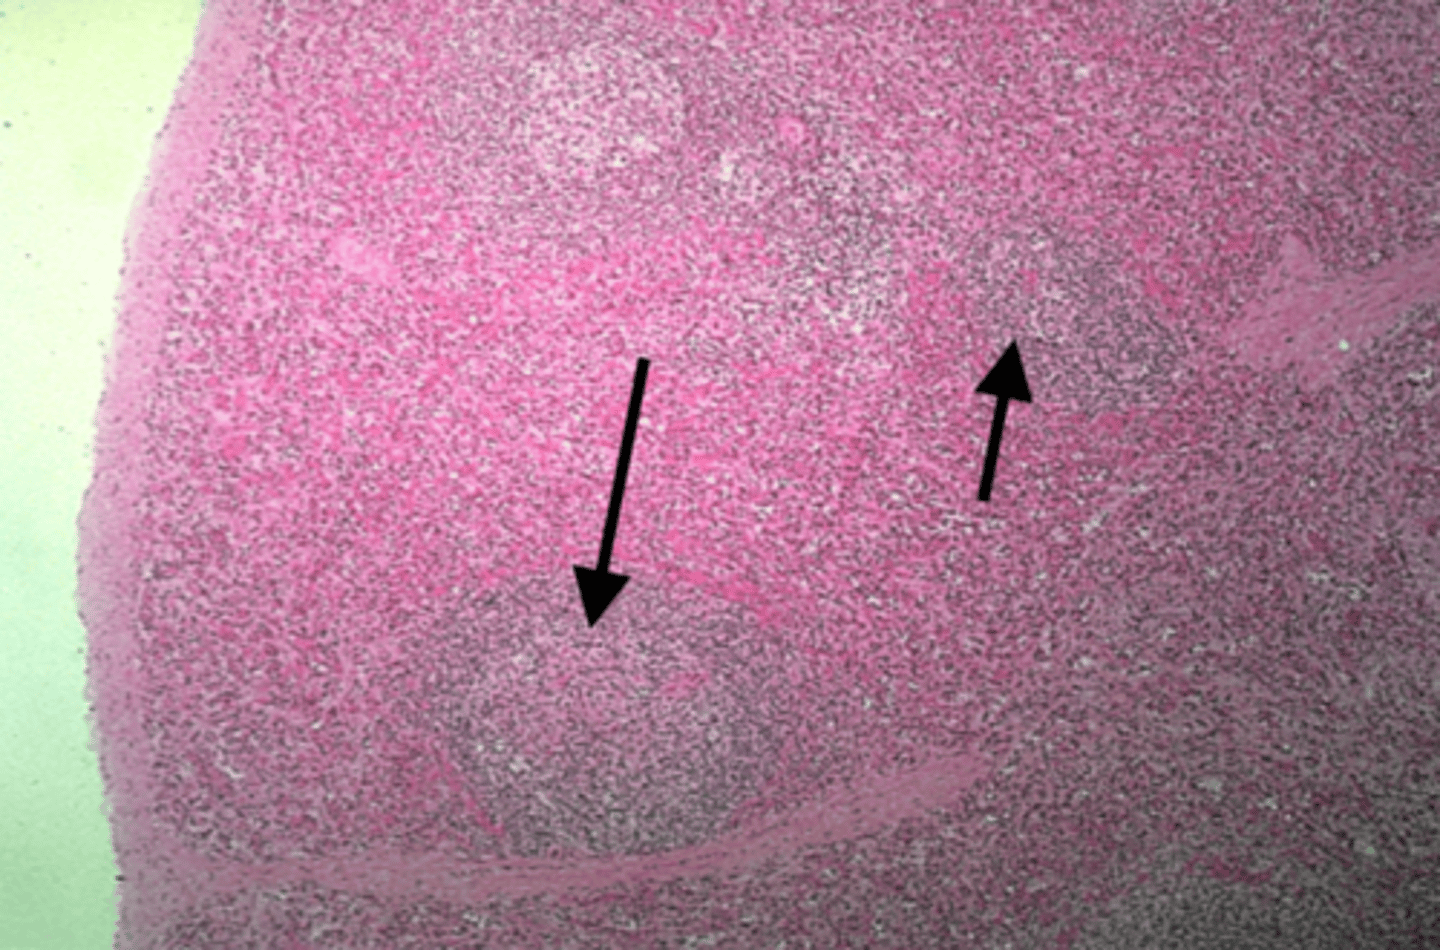

Spleen

What is this?

White pulp in spleen

What is it pointing at?